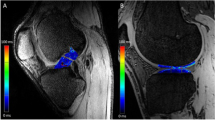

Examples of T1rho colour maps for the ACL and PCL in healthy and OA individuals are shown in Fig. 2. Means and standard deviations for each parameter (T1rho and T2), subregion (distal, middle and proximal thirds of the ligament) and group (OA and control) are presented in Table 4. The data is also displayed graphically in Fig. 3. Two variables for the OA group displayed significant variation across the ligament: mean T1rho times of the ACL (distal = 54.5 ± 9.9 ms, middle = 46.9 ± 9.6 ms, proximal = 47.0 ± 6.9 ms; p < 0.001) and mean T2 times of the ACL (distal = 43.2 ± 9.4 ms, middle = 38.0 ± 8.3 ms, proximal = 37.0 ± 5.0 ms; p = 0.017). Pairwise comparisons revealed for the former that the distal third of the ligament varied significantly from both the middle and the proximal thirds (p = 0.007 and 0.002 respectively). Pairwise comparisons for the latter revealed that the distal third of the ligament varied significantly from the proximal third (p = 0.007). For the control group, the mean T2 relaxation times for the PCL varied significantly across the ligament (distal = 26.4 ± 2.3 ms, middle = 32.7 ± 3.8 ms, proximal = 33.3 ± 5.2 ms; p = 0.009). Pairwise comparisons revealed again that the distal third of the ligament varied significantly from both the middle and the proximal third (both p = 0.031).

A Representative sagittal 3D spoiled gradient echo MRI images of the ACL of an OA (left) and healthy (right) subject with overlaid T1rho colormaps. Note higher and more heterogeneous values of T1rho in the OA subject. B As above but with T1rho colormaps of the PCL. Note higher T1rho values in proximal part of the PCL in the OA subject. C Variation in T1rho within the cruciate ligaments of an OA (left) and healthy (right) subject. Note increased variation/heterogeneity of T1rho values throughout the ACL of the OA subject